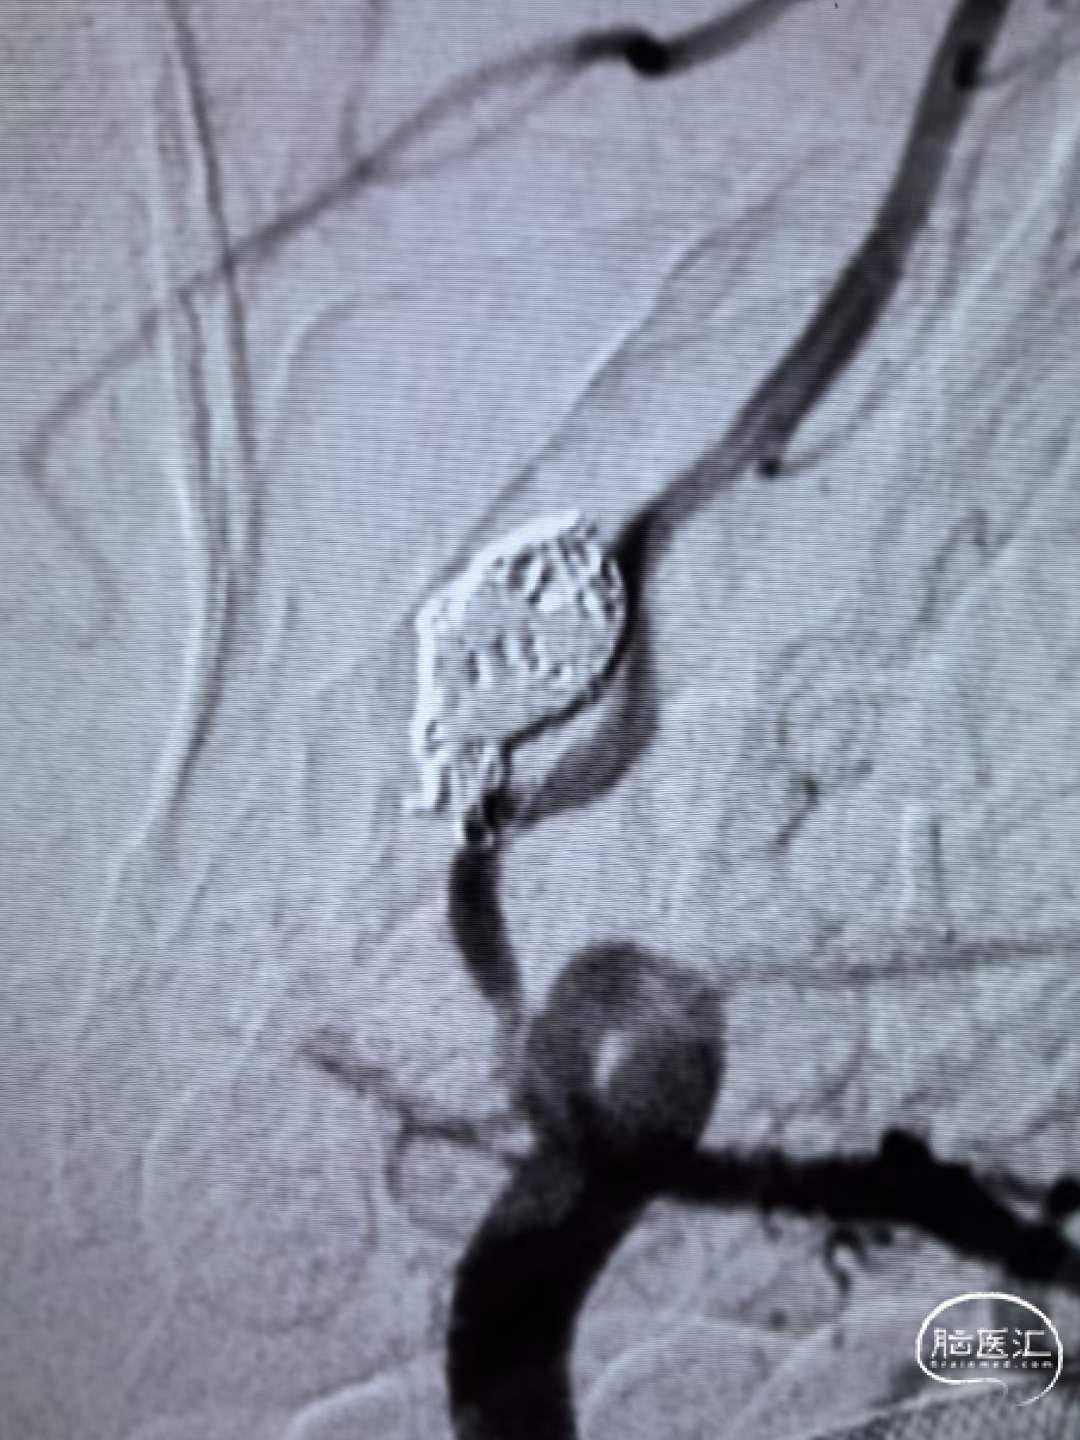

造影见前交通破裂动脉瘤,动脉瘤大小约7mm*12mm。